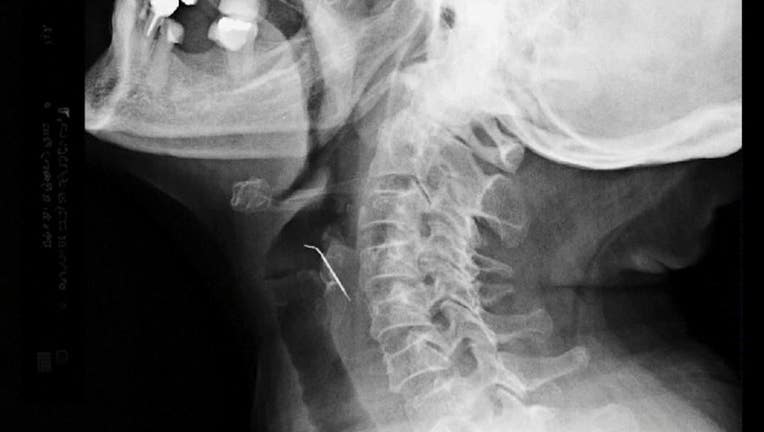

X-ray of nail stuck in throat of patient. (COURTESY: ESSALUD)

Tello's x-ray images showed the nail protruding into her throat. The woman, who now has a neck scar, has healed since then.